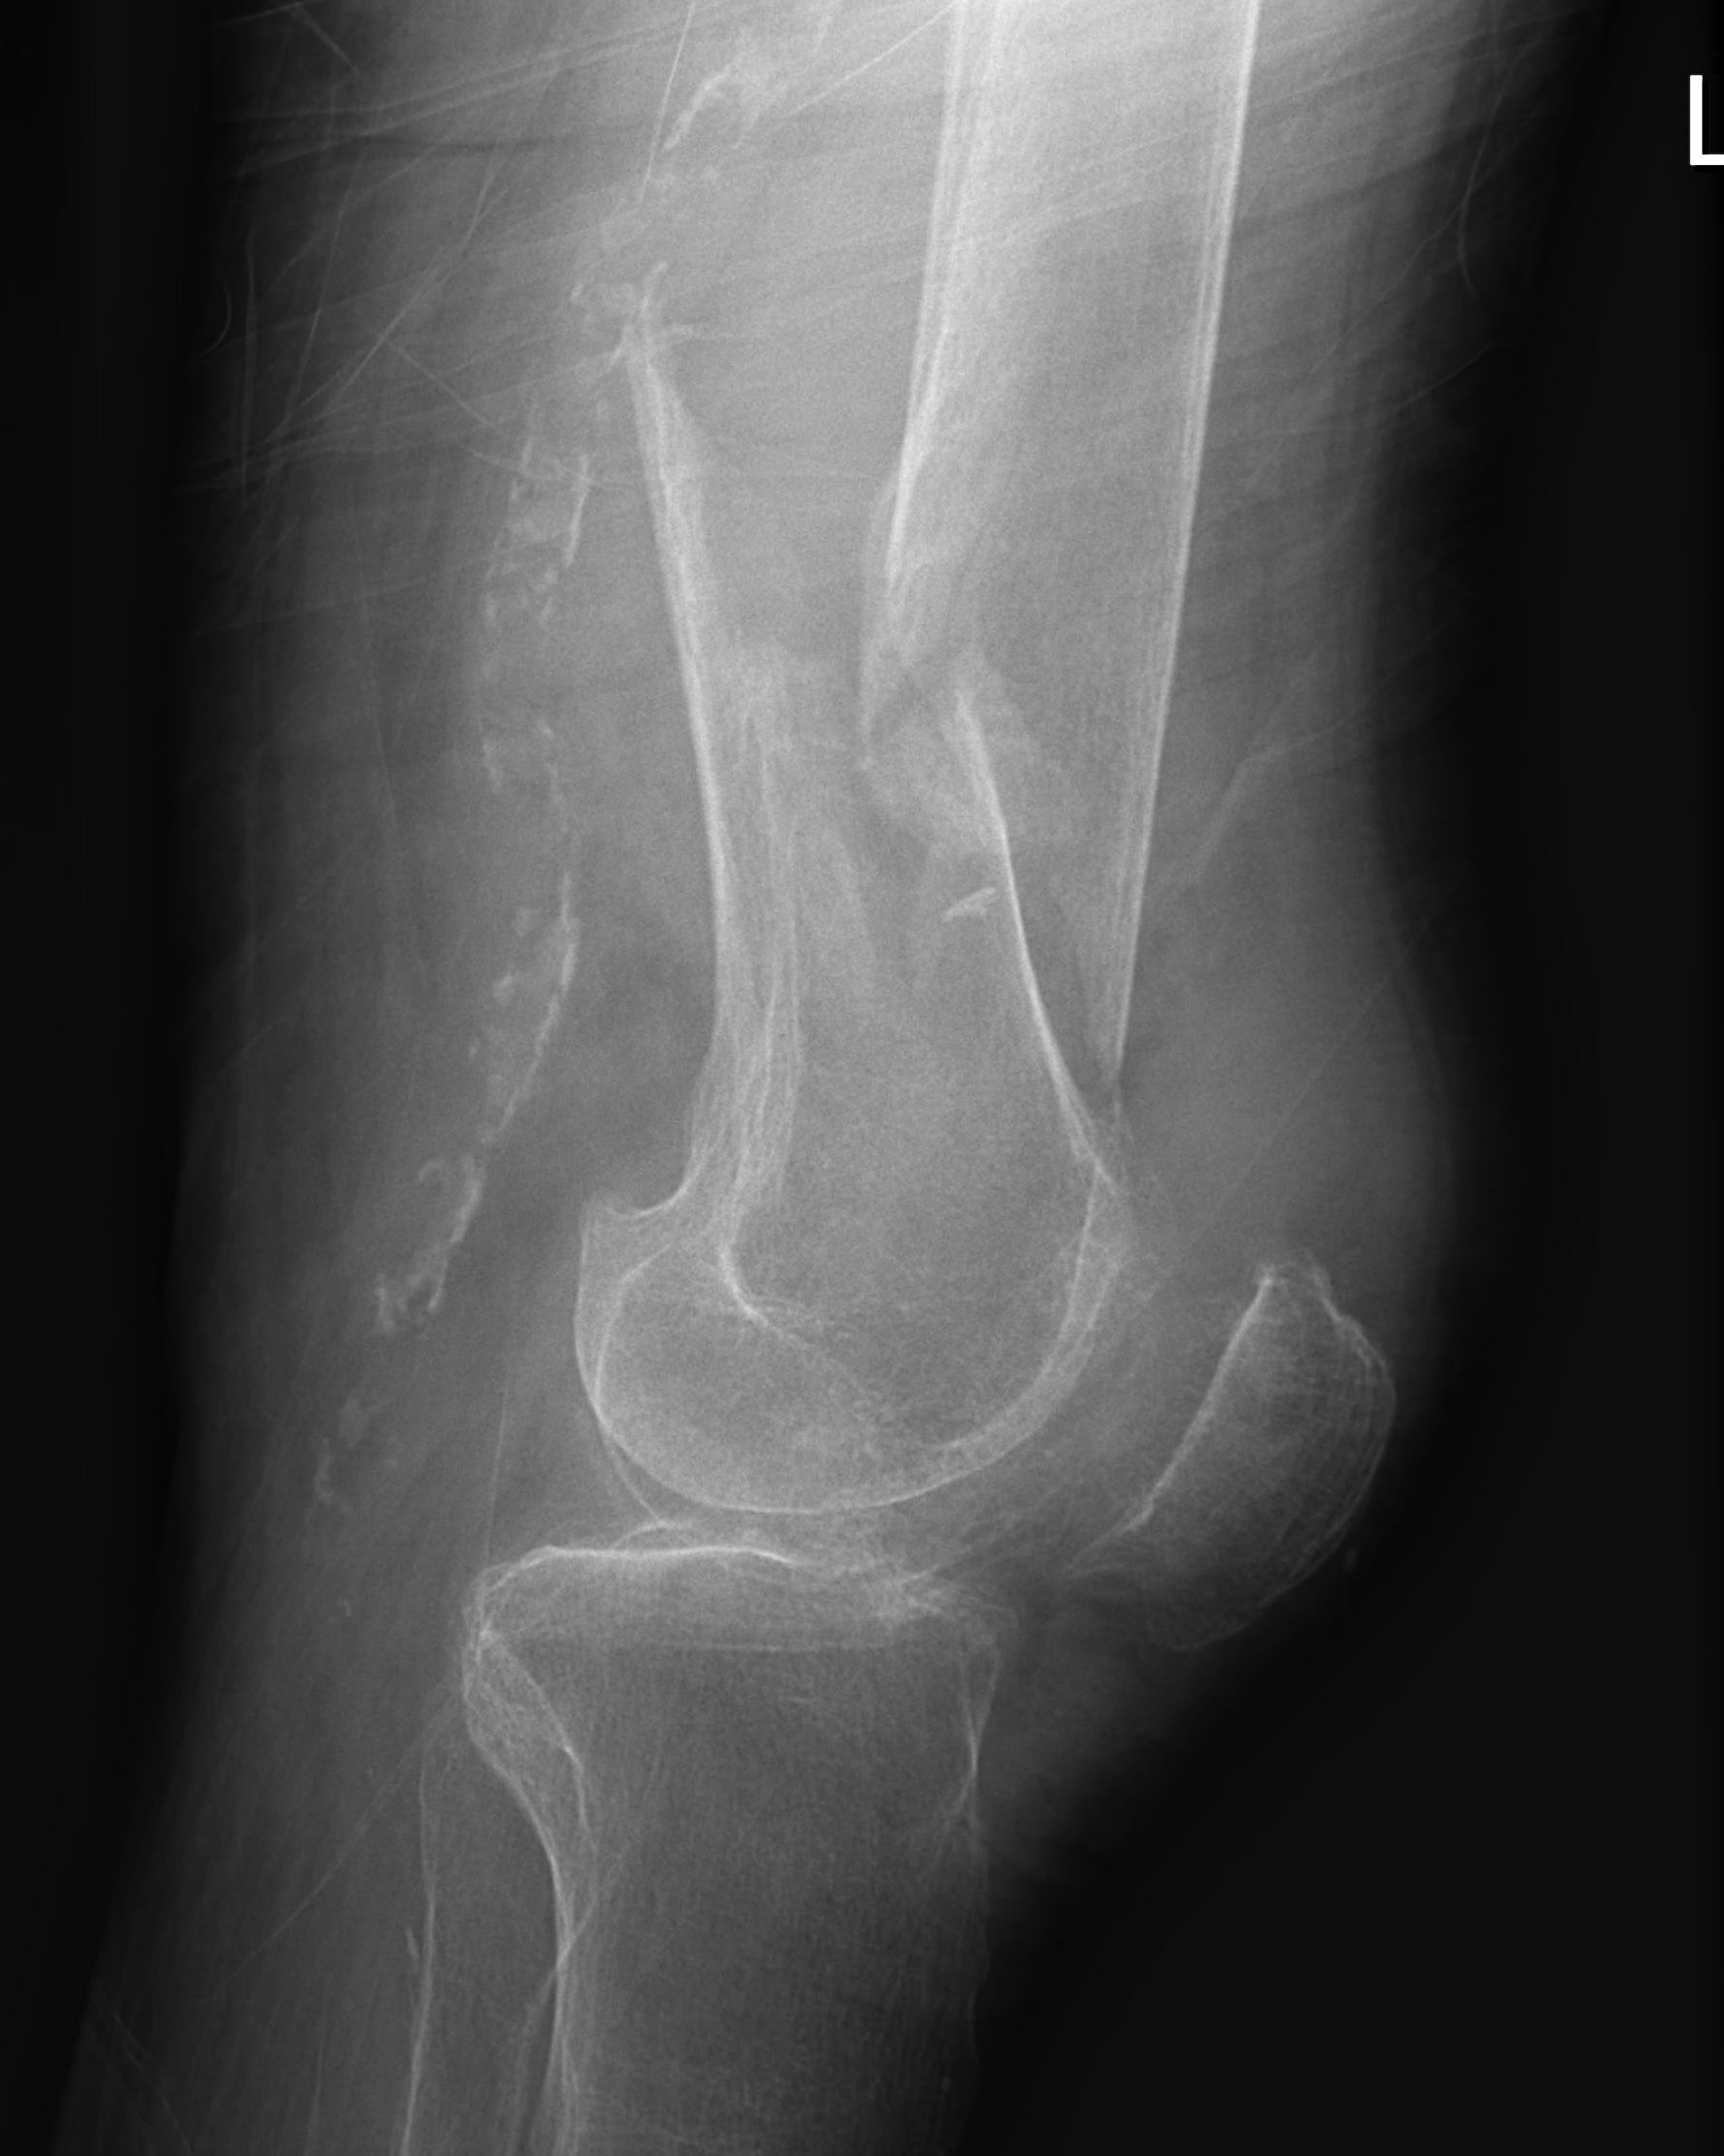

AO Type A: Supracondylar / Extra-condylar

Xray